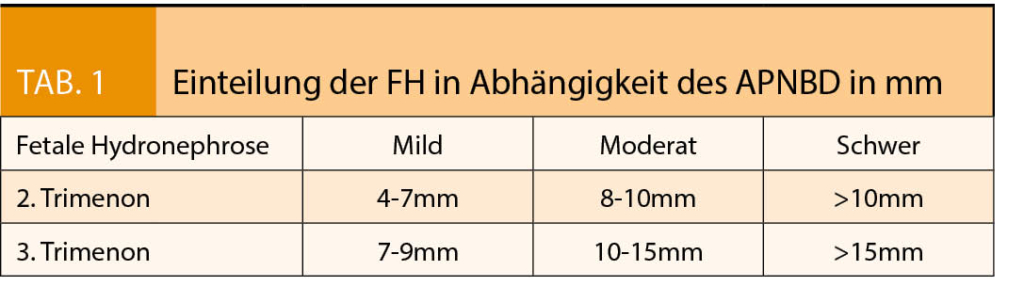

Deshalb kommt folgende Einteilung der FH im klinischen Alltag zum Einsatz (7, 8 , 9):